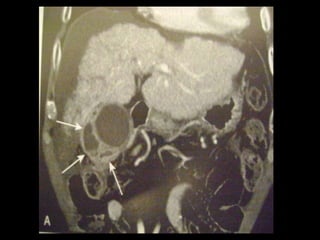

Colecistite aguda

US é a modalidade de imagem de escolha;

Em geral, a TC é realizada para avaliar pacientes

com suspeita de complicações do quadro de

colecistite aguda, como perfuração por exemplo.

Achados na TC: cálculos biliares, espessamento da

parede, alterações inflamatórias

perivesiculares, bile com alta

atenuação, borramento da interface VB-fígado e

aumento transitório da atenuação do fígado

perivesicular;

http://radiographics.rsna.org/content/28/1/135.full